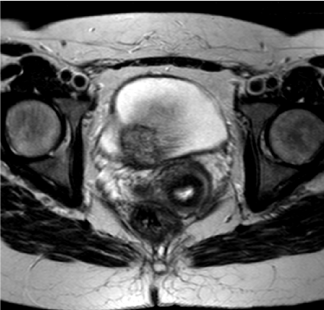

A 37year-old non-smoking primigravid female, underwent routine foetal anomaly Ultrasonography at twenty weeks gestation. This scan confirmed a viable twin pregnancy with normal foetal development, however identified an indeterminate lesion on the posterior bladder wall (Figure 1). The patient did not describe any visible haematuria, nor did she suffer from any lower urinary tract symptoms. She was otherwise in good health with no significant past medical or surgical history.

Figure 1 First transabdominal ultrasound scan conducted. Foetus at 20 weeks. Bladder lesion visualised.